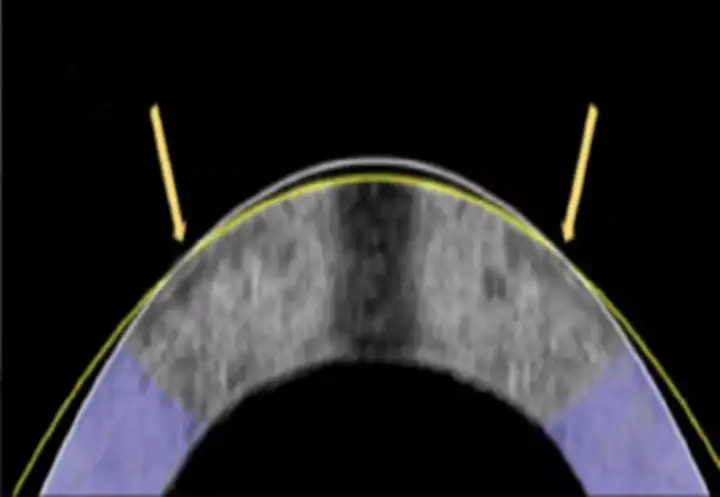

Новый метод, позволяющий ремоделировать роговицу посредством слабого электрического потенциала, известен как электромеханическое изменение формы. Роговица — это прозрачная куполообразная поверхность в передней части глаза, действующая как прозрачное окно, помогающее фокусировать входящий свет. Она состоит из плотно упакованных коллагеновых волокон и отличается прочностью и гладкостью. Это естественная линза глаза, и именно здесь происходит преломление света, необходимое для фокусировки изображения на сетчатке.

Метод электромеханического изменения формы успешно выровнял роговицу кролика. Метод электромеханического изменения формы успешно выровнял роговицу кролика.© Daniel Kim and Mimi Chen

Кривизна роговицы приводит к таким состояниям, как близорукость (миопия) и дальнозоркость (гиперметропия), и до сих пор основным методом лечения этих заболеваний был лазерный кератомилёз. Это дорогостоящая и инвазивная процедура, поэтому вместо этого исследователи предложили работать с самим составом роговицы, чтобы изменить форму купола. Учёные обнаружили, что, пропуская слабый электрический ток через специально разработанный платиновый электрод, можно изменить pH ткани, повышая её кислотность и делая её гибкой ровно настолько, чтобы её можно было изменить.